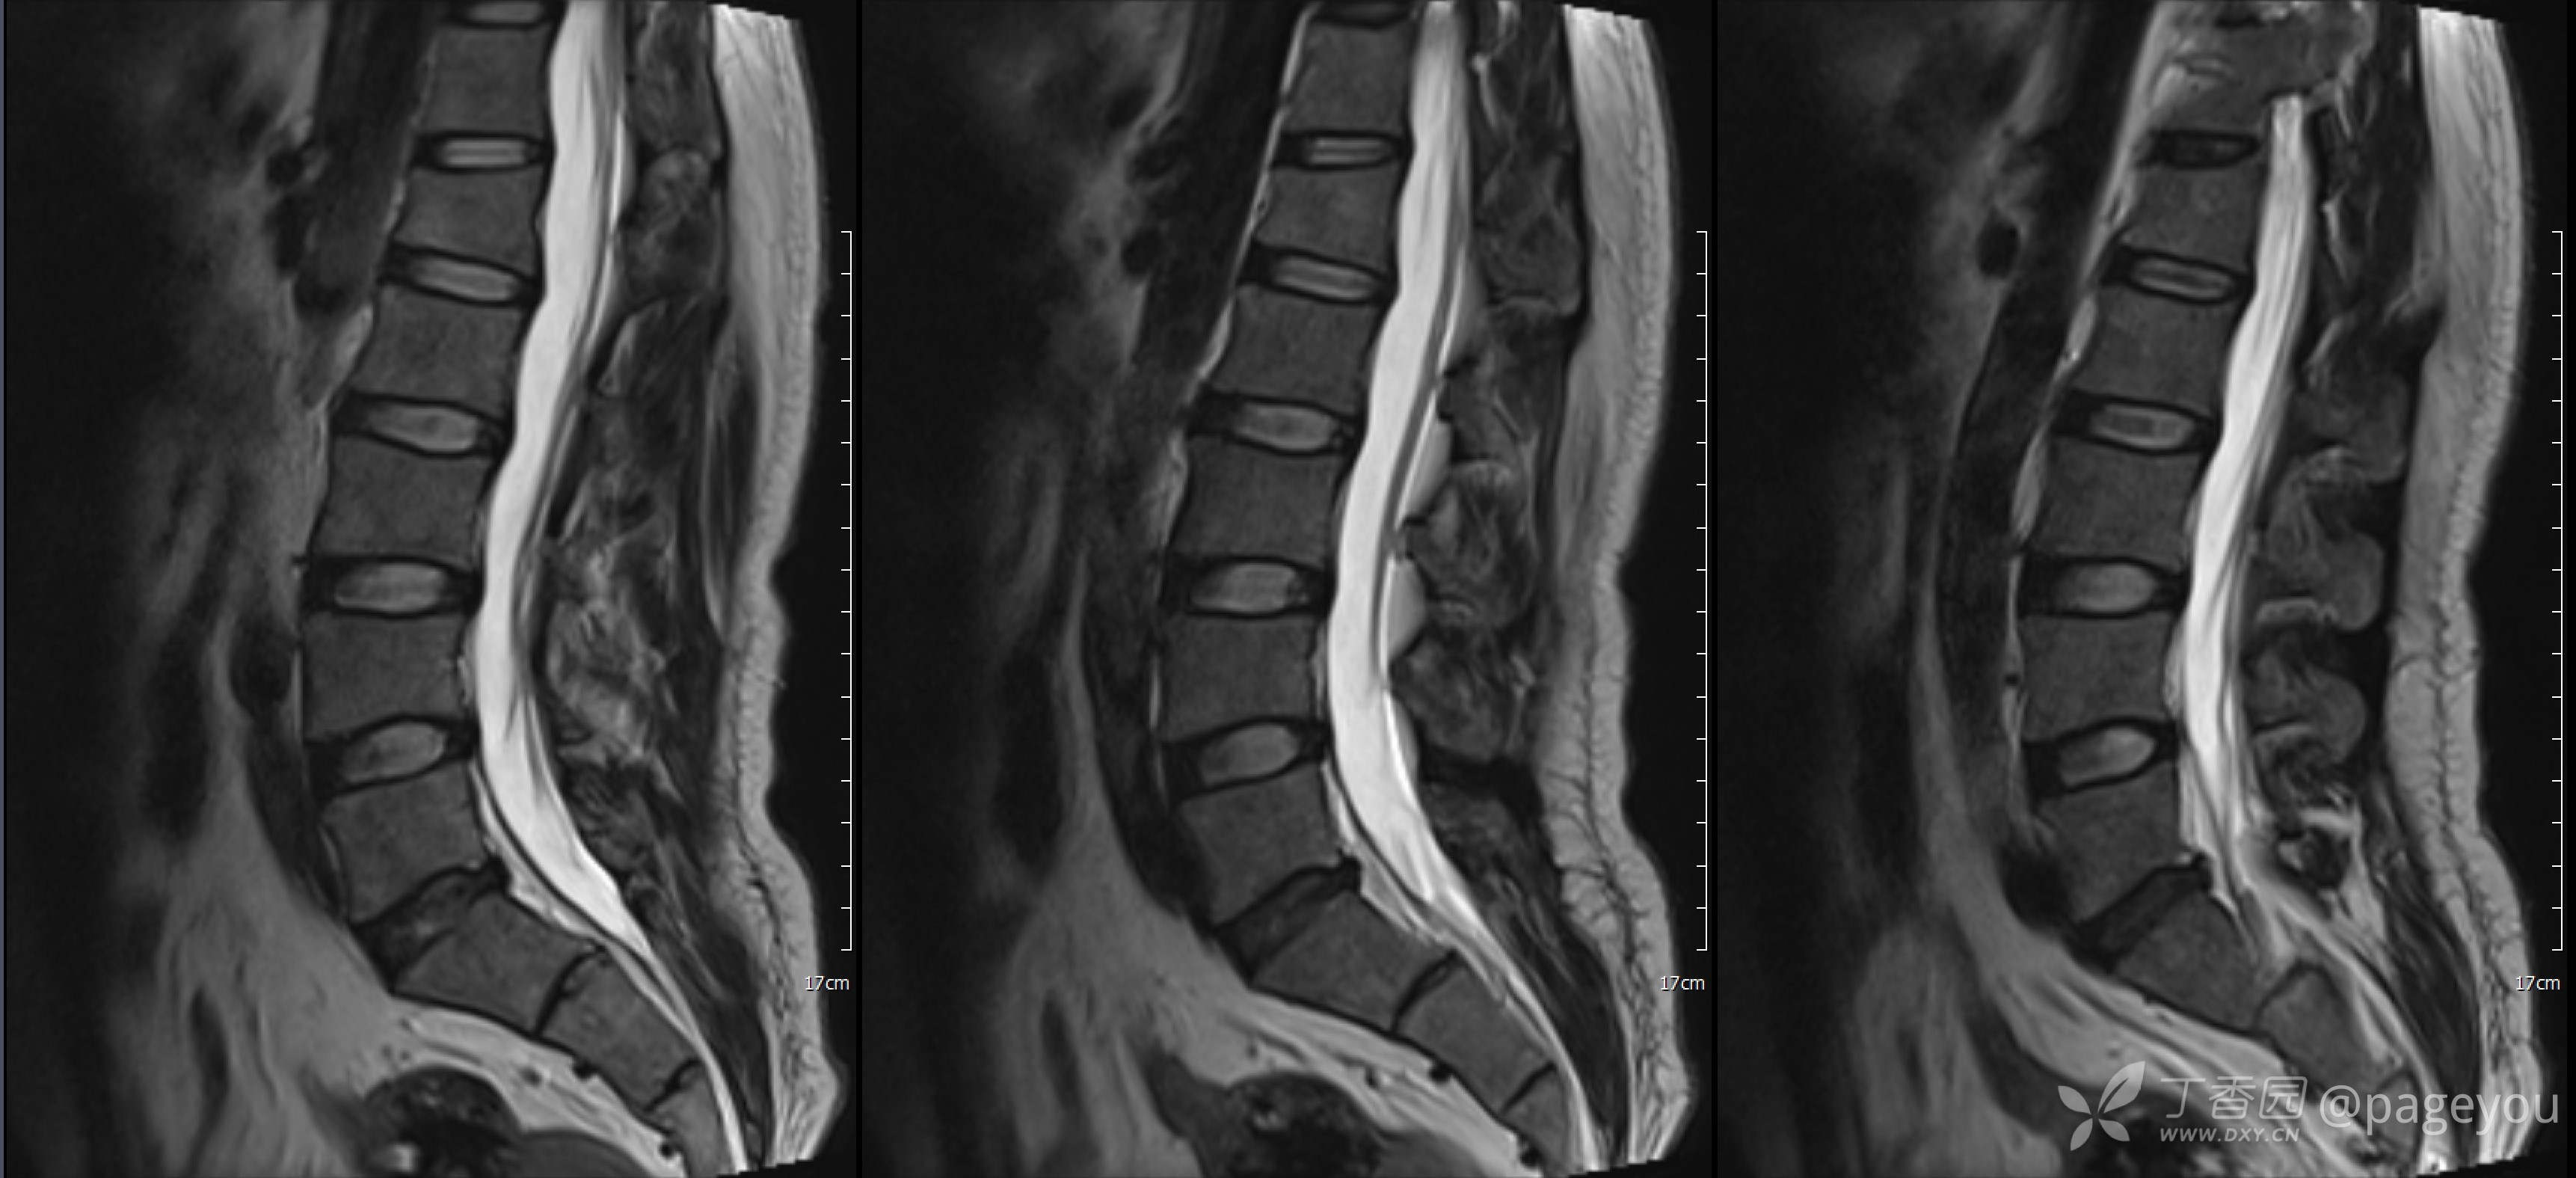

入院查腰椎MRI: